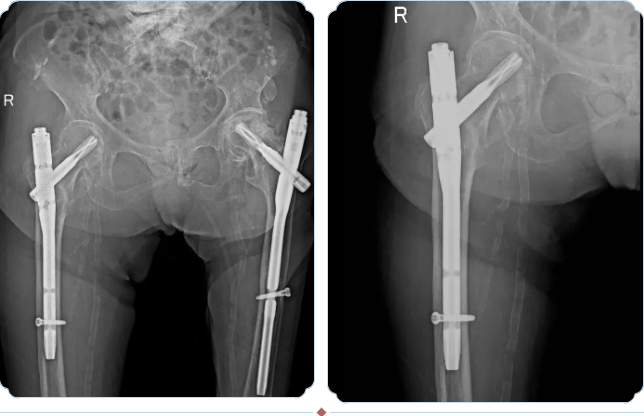

骨科团队经过充分评估,决定为患者实施PFNA(股骨近端防旋髓内钉)内固定术。这种微创手术具有创伤小、出血少、固定牢固、允许早期活动的优势,特别适合老年骨质疏松性骨折患者。

精细化手术操作,45分钟完成关键治疗

手术当天,多学科团队严阵以待。麻醉科医生首先实施精准的神经阻滞,患者生命体征始终保持平稳。骨科手术团队通过仅3-4厘米的小切口,在C型臂X光机引导下精准置入髓内钉,骨折复位良好,固定牢固。整个手术仅耗时45分钟,出血量不到50毫升。

(术后DR)